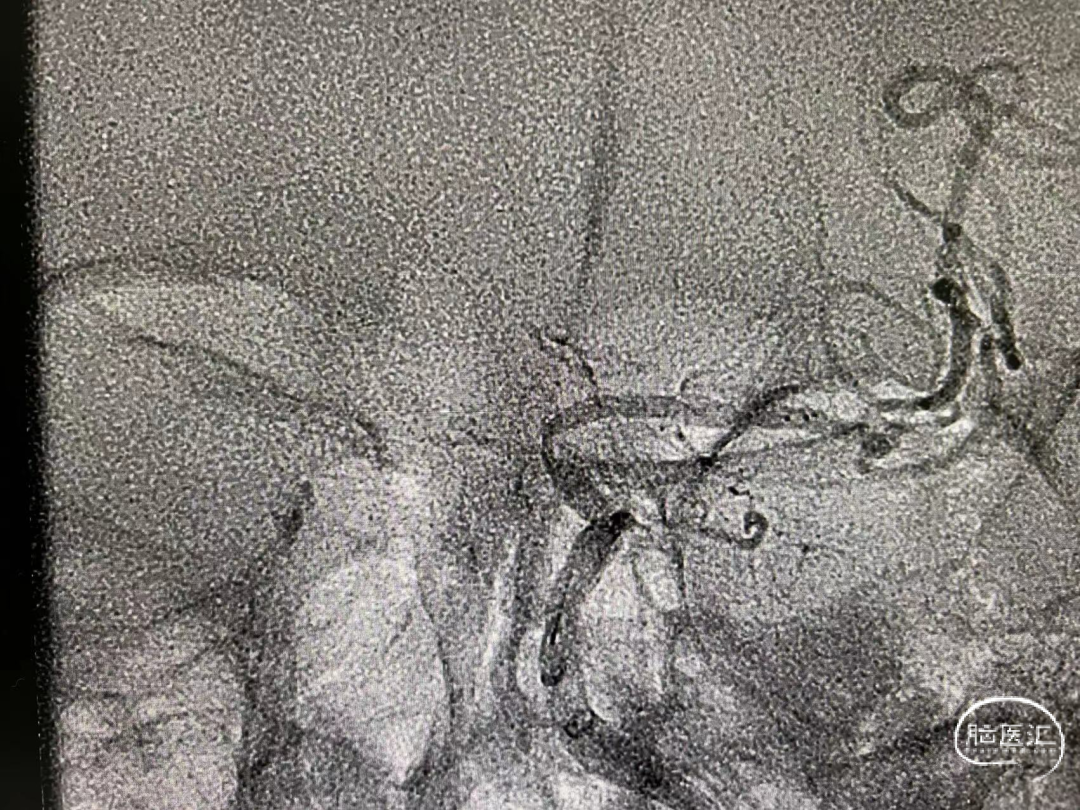

全脑造影:左侧颈内动脉末端闭塞,前后交通未开放。

Synchro 200cm微导丝携带支架微导管至M2段,中间导管跟进至左侧颈内动脉闭塞段近端,微导管造影确认真腔。

送入Trevo4/20cm支架到位后释放,造影见支架中断蜂腰征,考虑原位狭窄可能,中间导管后端推注替罗非班0.5mg,同时静脉给予替罗非班持续泵入。支架压迫5分钟,负压抽吸下后撤,同时跟进中间导管至M1起始段,支架上可见块状血栓组织。中间导管后端接注射器反复抽吸清理残余血栓。

造影见左侧大脑中动脉及其分支血流复现,颈内动脉末端中度狭窄,观察20分钟复查造影见前向血流维持良好,未再给予补救措施。